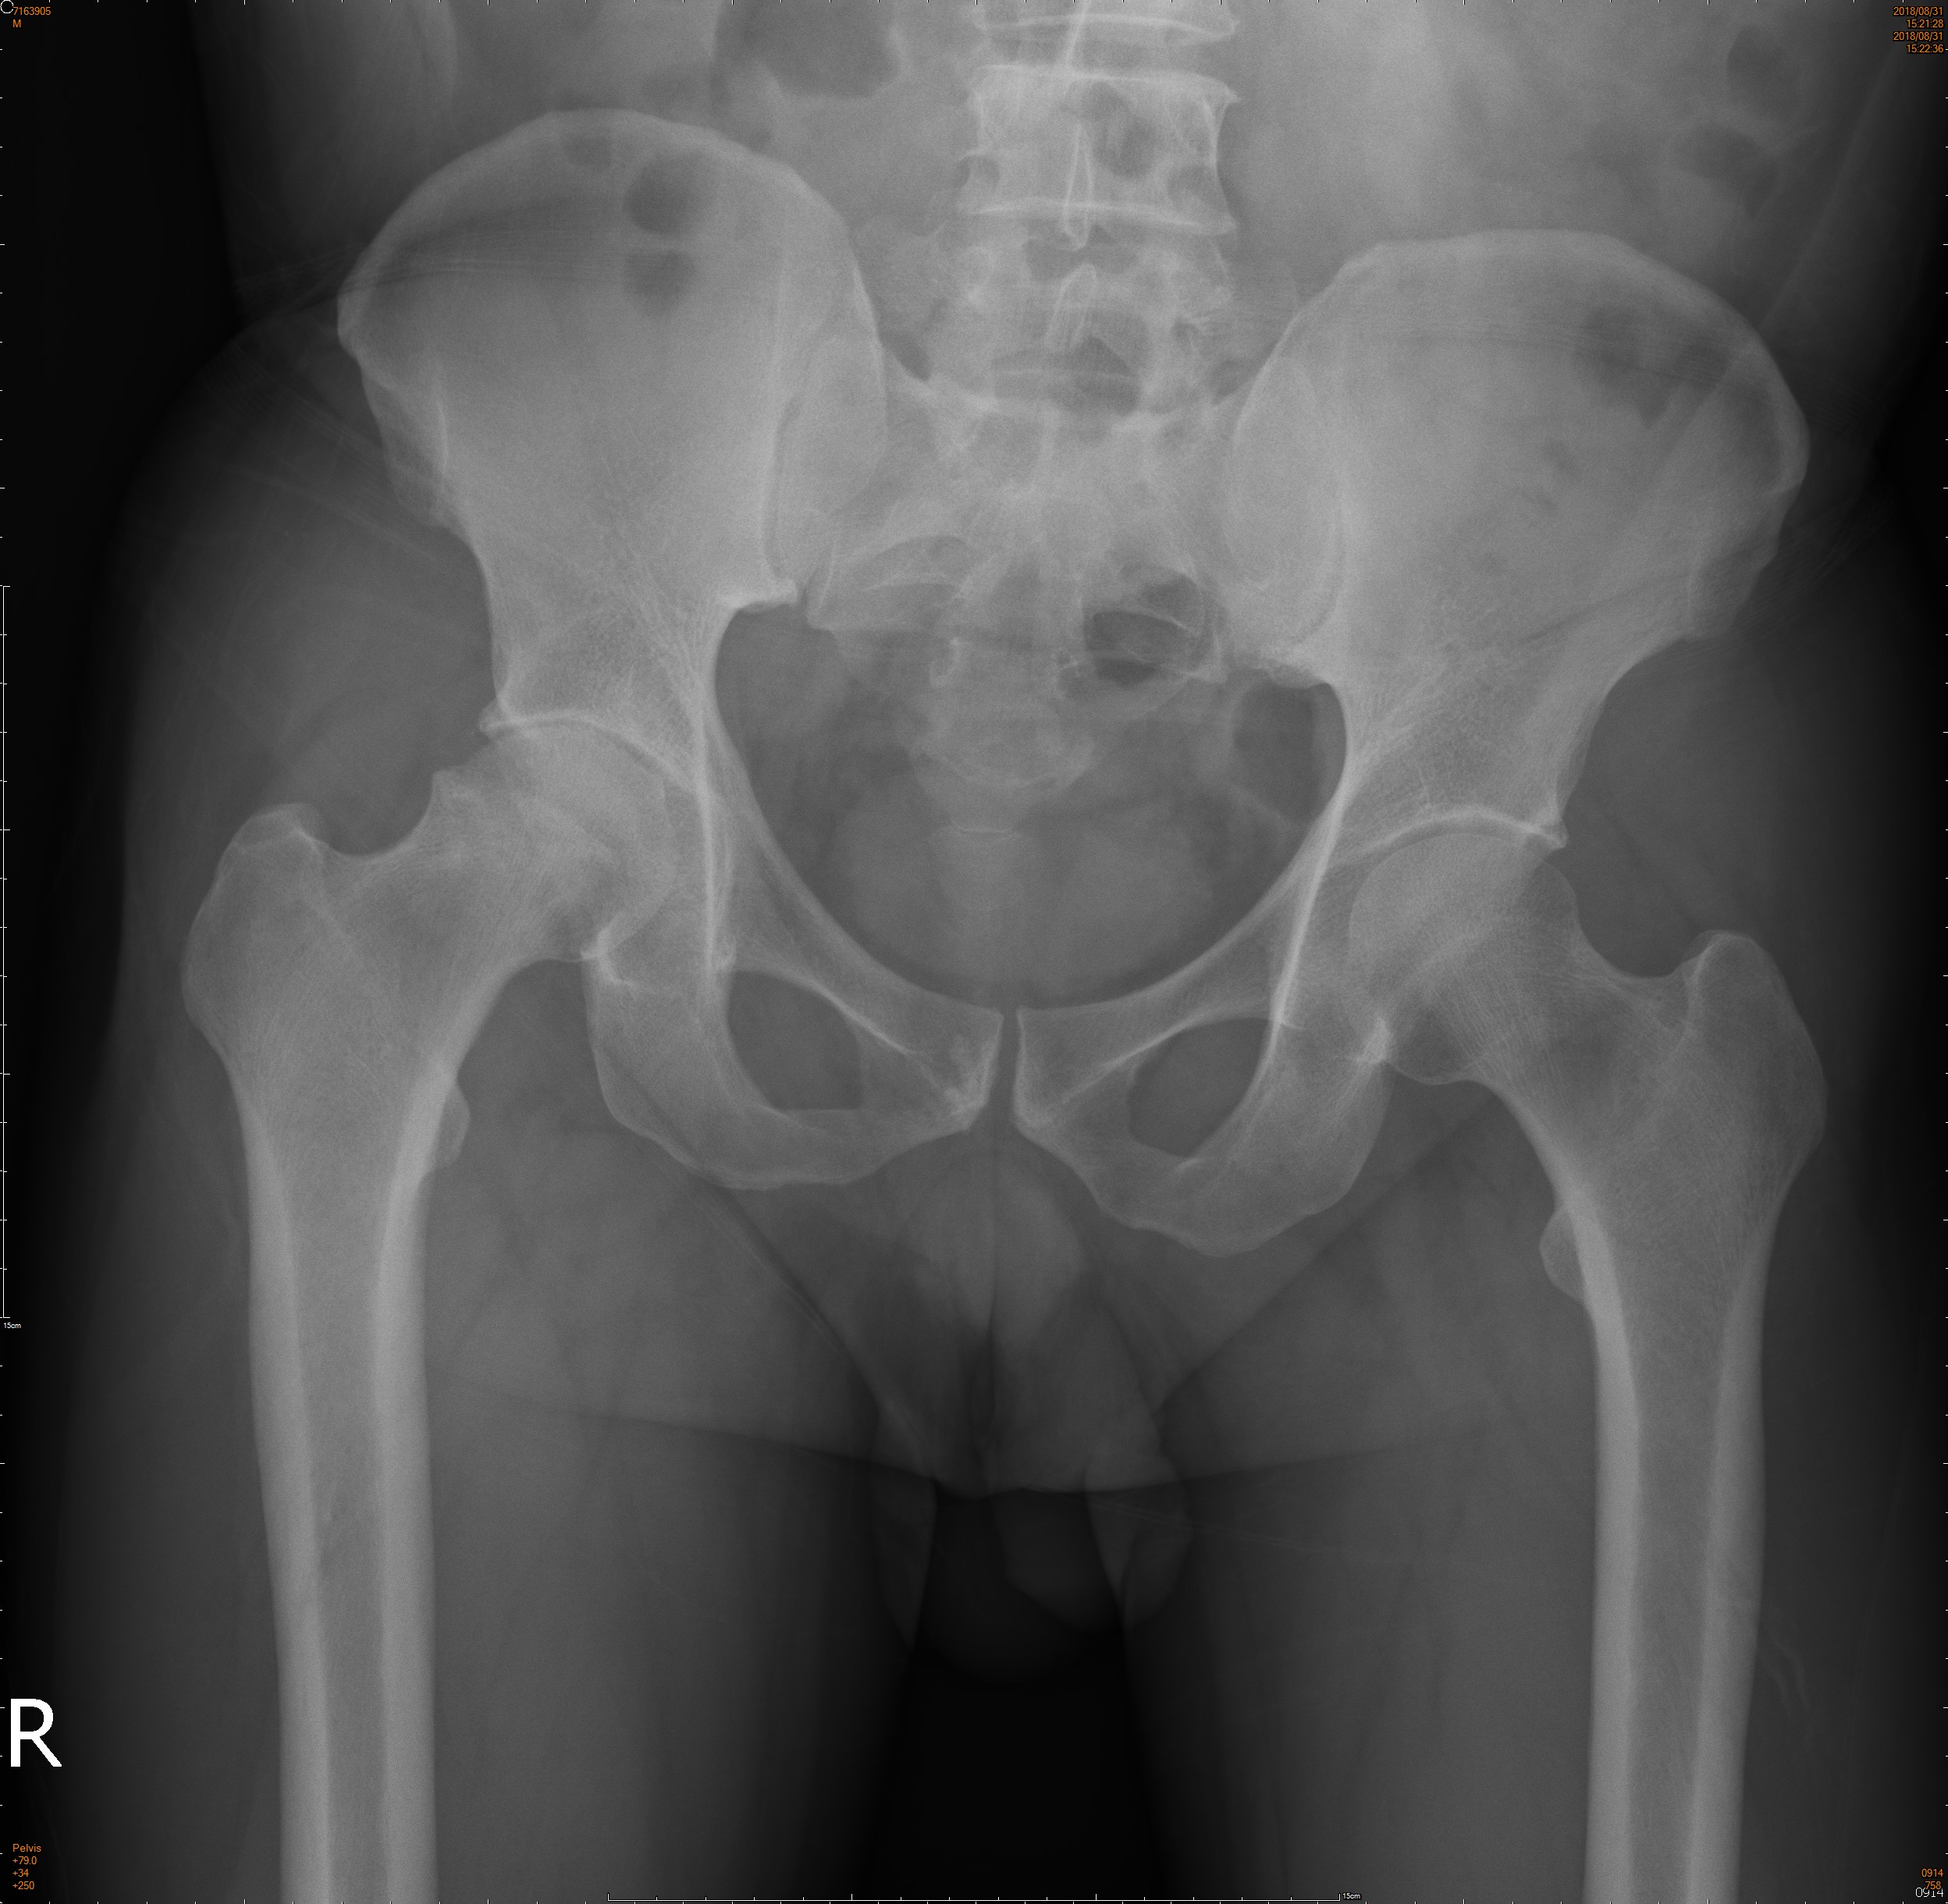

47歲的陳先生兩個月前右側髖關節開始疼痛,近來更是加劇,連走路都開始跛行了,理學檢查發現髖關節轉動會引發疼痛;X光則發現股骨頭已經塌陷了,後來接受人工關節置換才解決問題。

患者的主要症狀以患肢負重疼痛為主,意思就是走路會痛,疼痛的部位在鼠蹊部或是髖部深處,有時膝蓋也會有牽引痛。理學檢查可以發現髖部活動受限或是轉動檢查(Patrick test)會痛。如果骨頭結構已經被破壞及吸收了,是可透過X光檢查清楚發現的(圖一);若需要早期發現,則必須仰賴核磁共振(MRI)檢查(圖二)。

(圖一)